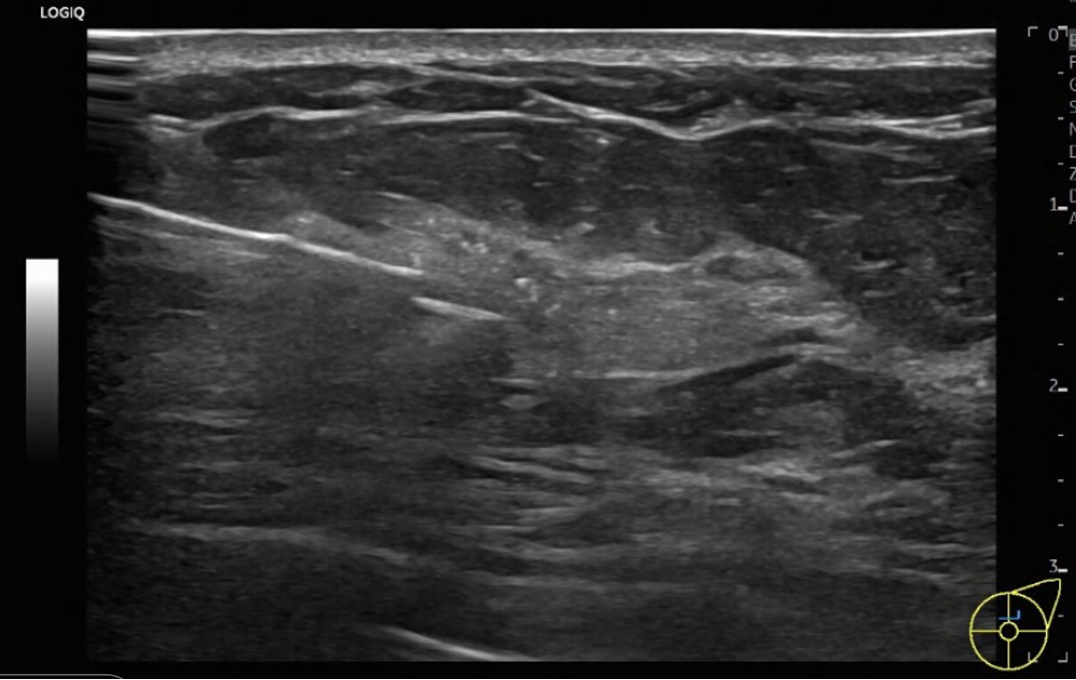

患者因发现左乳肿物1周就诊我院,门诊复查彩超提示:左乳晕区内上象限可见一低回声区,范围为5+×1.5cm,形态不规则,边缘不规整,考虑乳腺癌(BI-RADS 4C);余左乳结节,较大位于外上象限,最大约1.5×1.1cm。左腋窝可见多发淋巴结声像(可疑1个):较大为2.6×0.9cm,性质待查。

新辅助治疗期间因患者个人原因仅同意乳腺彩超监测疗效,结果如下:

治疗约5个月时,术前彩超还提示:左侧锁骨上淋巴结,皮髓质界不清,淋巴门受压消失,大小约1.6×0.7cm,性质待查。